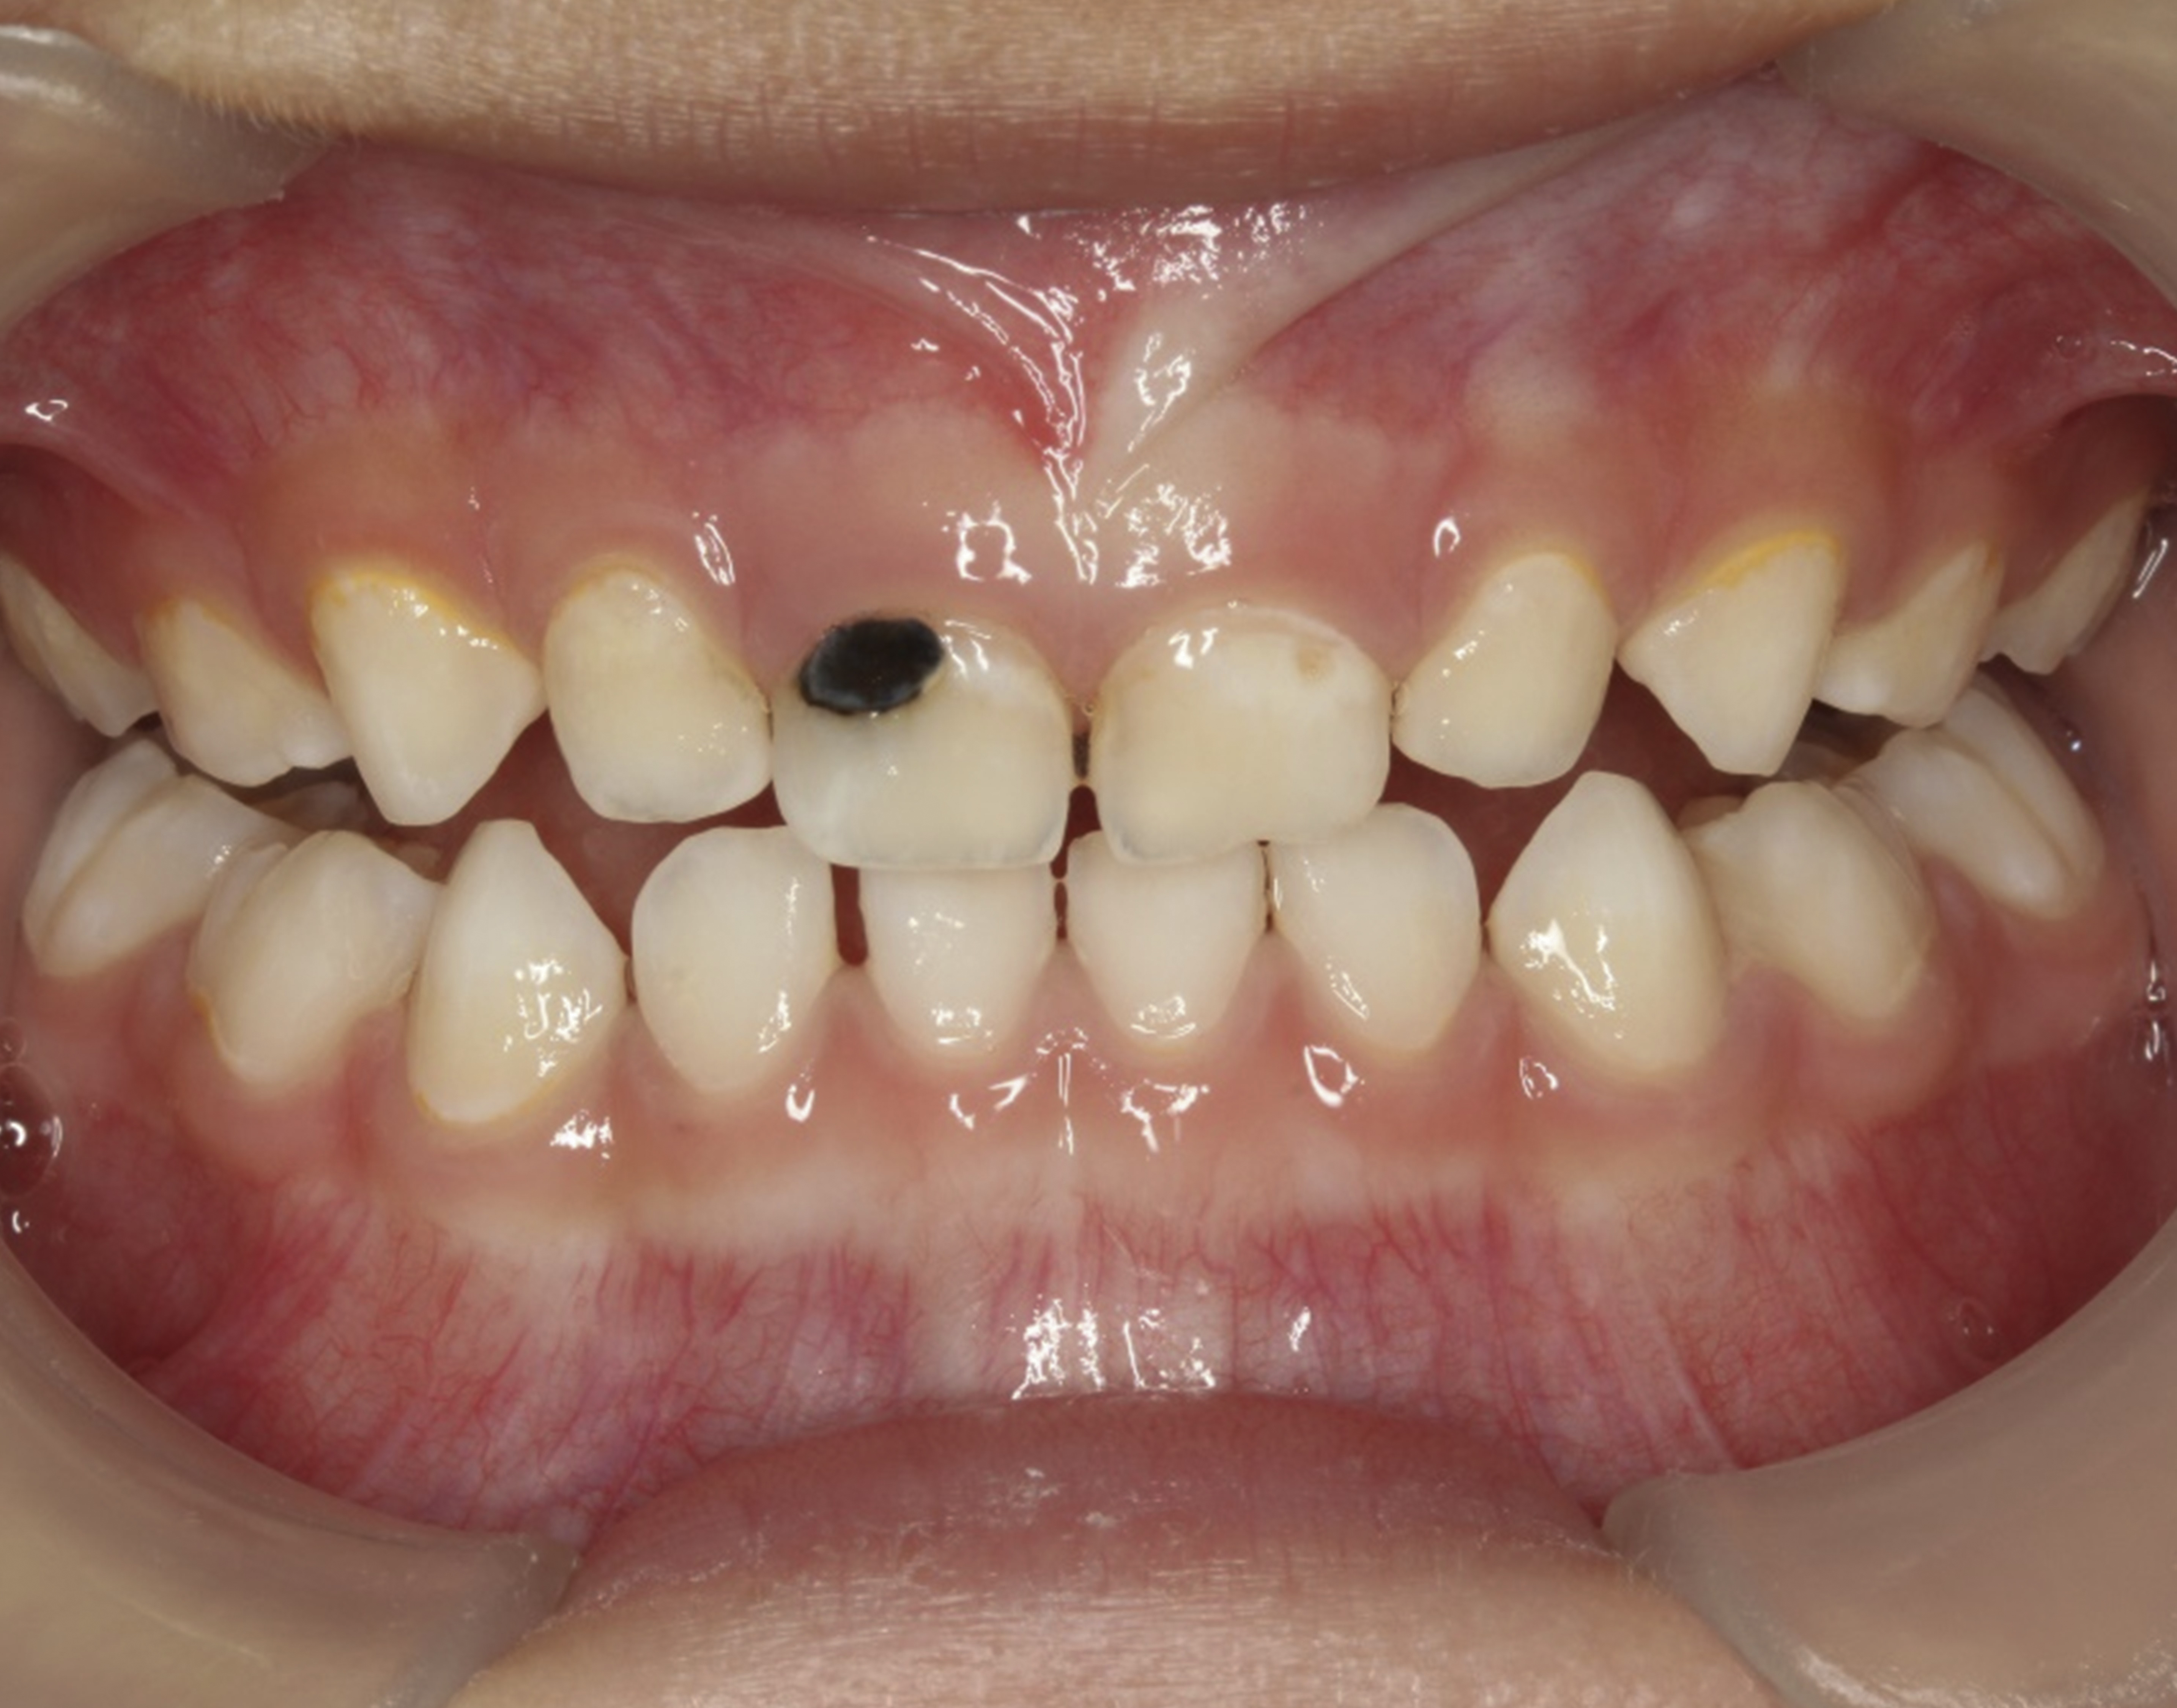

There are several advantages of using SDF in dental treatment. First, it showed an antimicrobial activity against mono-species, dual-species, and multi-species cariogenic biofilm.14-16 Silver ions are bactericidal metal cations that inhibit biofilm formation.17 Studies have indicated that silver interacts with sulfhydryl groups of proteins and DNA, thus altering hydrogen bonding and inhibiting respiratory processes, DNA unwinding, cell-wall synthesis, and cell division.18 At the macro level, these interactions affect bacterial killing and inhibit biofilm formation.17 Second, fluoride promotes caries lesion remineralization. Fluoride has been indicated to react with hydroxyapatite and generate calcium fluoride, which is a reservoir of fluoride, and facilitate further remineralization.19 An ex vivo study reported surface microhardness of the surface layer of the arrested caries after SDF applications was comparable with the unaffected sound dentin20 (Figure 1 and Figure 2). This is consistent with another study, in which a high remineralized zone was observed on the surface of arrested caries from exfoliated teeth with SDF treatment21 (Figure 3 and Figure 4). Third, its application procedures are simple and do not require injection or drilling, and the treatment does not involve expensive support infrastructure equipment such as piped water and electricity. The simplicity of the treatment is conducive to treating caries in apprehensive young children who may have intense dental fear, uncooperative patients with special needs, or elderly patients who have difficulty adapting to traditional dental care. It also allows trained workers to deliver the treatment to people who live in the area but who may not be able to easily access dental service.22 Patient compliance and satisfaction is often good when the patient is provided a clear explanation of the treatment outcome.23,24 Finally, the cost of SDF treatment is low and should be affordable in most communities.

Fig 1. Ground section of a primary incisor with arrested caries lesion after SDF treatment. Fig 1: Arrested caries that had SDF treatment. Fig 2: Microhardness of dentin (in median Knoop hardness number) in soft and SDF-arrested caries according to the distance from the lesion surface. (images from Chu and Lo, 200820 [reprinted with approval])

Fig 1 and Fig 2. Ground section of a primary incisor with arrested caries lesion after SDF treatment. Fig 1: Arrested caries that had SDF treatment. Fig 2: Microhardness of dentin (in median Knoop hardness number) in soft and SDF-arrested caries according to the distance from the lesion surface. (images from Chu and Lo, 200820 [reprinted with approval])

Fig 5. Use of 38% SDF to arrest coronal caries in primary teeth of a young child. The arrested carious lesion had a hard, blackened, and impermeable layer.